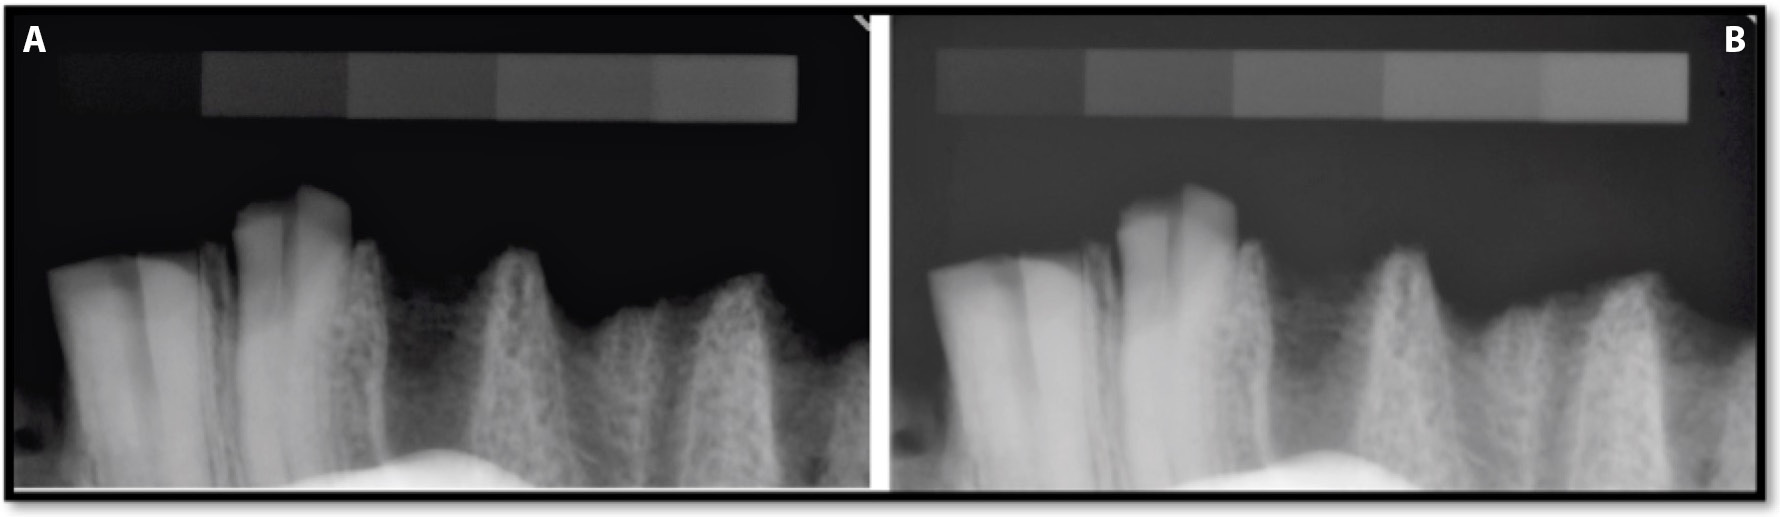

The impact of the optimization algorithm on the Group A radiographs, which were captured at exposure times of 0.05 s and 0.125 s, are presented in Table 2 and Figure 7. The radiographs of the bone specimen captured with an exposure time of 0.125 s – with and without the automated adjustment option – are presented in Figure 8.

The results demonstrate that the algorithm causes a reduction in the difference between particular exposure times as well as a reduction in optical density. The lower the optical density, the larger the decrease in optical density was recorded (Figure 7). The decrease in optical density recorded for the exposure times of 0.05 s and 0.125 s at step 1 amounted to 80.5% and 83.1%, respectively, and at step 9 it was 4.3% and 4.8%, respectively. A detailed analysis of step 2 of the imaging phantom showed the difference between the optical density value for exposures of 0.05 s and 0.125 s to be 13.7 (96.0 ±3.9 compared to 82.3 ±3.2) with the automated adjustment function switched off, and only 5.9 (2.3 times lower) (28.7 ±2.8 compared to 22.8 ±2.0) when the function was on. These changes can be seen in the radiographs of bone specimen (Figure 7).

The use of automated adjustment resulted in the image becoming darker and more contrastive in areas with an optical density higher than 50 (phantom steps 5–9). The higher image contrast displaying the clearer structure of the object. However ROI’s with low optical density became blurred (decrease of contrasts between steps 1 and 2, 2 and 3, 4 and 5) in comparison with the radiographs without the automated adjustment option. The algorithm made the 1st degree of the pattern and a thin alveolar plate invisible to the observers (Figure 7).

When analyzing and comparing images, it should not be forgotten that the software usually compensates for variations in exposure parameters with automated optimizing algorithms. The option (algorithm) of automated adjustment, which corrects a digital image, is also included in the Dimaxis software that was used in this study. The default application of an optimization algorithm significantly reduces the differences between exposure times if they are in the range of 0.05–0.125 s. The use of longer exposure times (0.16 s and 0.2 s) highlights the limitations of the software and the sensor used in this study, as it caused image disturbances of objects with an optical density of less than 50. Because an object with low radioabsorption becomes imperceptible at exposure times of 0.16 s or 0.2 s, those radiographs were recognized as “lighted.” A similar selection was made in the article by Morea et al. due to the ghost images which were produced by an exposure time beyond the latitude of the sensor.16 Overexposure of the 0.16-second and 0.2-second images can also be caused by the lack of a soft-tissue-equivalent absorbing part of the radiation between the X-ray beam and sensor. The soft tissue model was not included in the current study. This assumption is confirmed in Figure 7, Figure where the operation of the algorithm is visible and makes the first-degree pattern and a thin alveolar plate invisible.